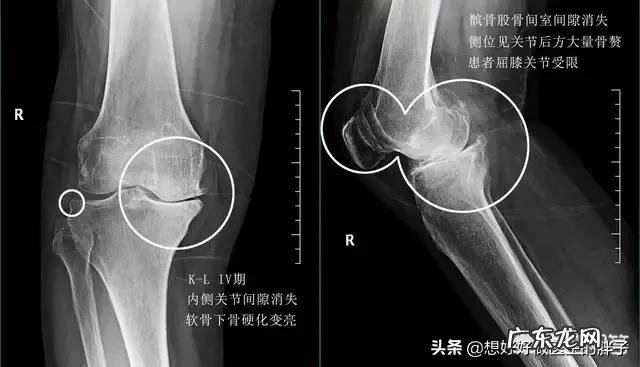

临床上一般根据膝关节x线的表现,关节内骨赘增生的程度?关节间隙是否狭窄?将骨关节炎在临床上分为4期,针对于骨关节炎1期,2期和3期,患者主要还是采取保守治疗加康复锻炼的办法,而骨关节炎4期的患者关节间隙会有明显的狭窄,关节内的软骨几乎磨损殆尽,只有通过关节置换或者是部分关节置换的办法,才能帮助患者解决问题,下图就是典型的骨关节炎4期影像学资料,关节间隙已经消失,关节周边大量的骨赘形成患者的关节功能,已经受到了严重的影响,这一类的关节应该进行关节置换 。